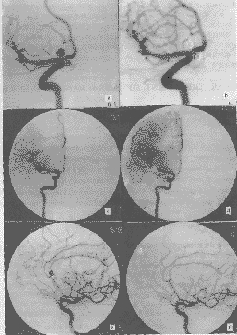

颅内动脉瘤